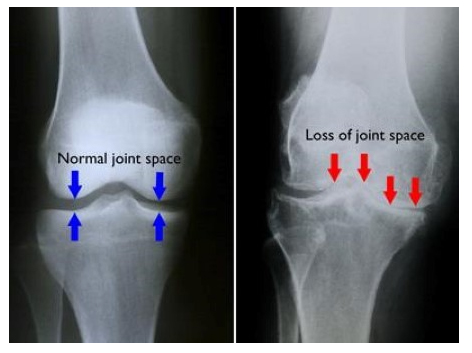

Osteoarthritis or wear and tear of the knee typically occurs in old age. It is characterized by a general wear and tear of the knee. In addition to the thinning and disappearance of the cartilage, the quality of the meniscus also deteriorates with age. As a result, these structures lose their shock-absorbing function, which leads to overloading of the underlying bone.

An important examination in osteoarthritis are the Xrays. These are best performed while the patient is standing so that the narrowing of the joint can be properly appreciated. An MRI scan might be indicated in cases where expected cartilage damage are present.

A knee prosthesis is the definitive treatment for osteoarthritis of the knee. Knee osteoarthritis means the wearing away of the smooth cartilage layer in the joint. As a result, the joint surfaces can no longer slide smoothly over each other, and moving becomes increasingly difficult and painful. A full knee replacement is an artificial joint that replaces the damaged cartilage of the knee joint.